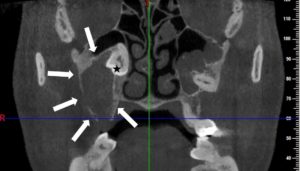

Οδοντοφατνιακή Χειρουργική – Έγκλειστα δόντια